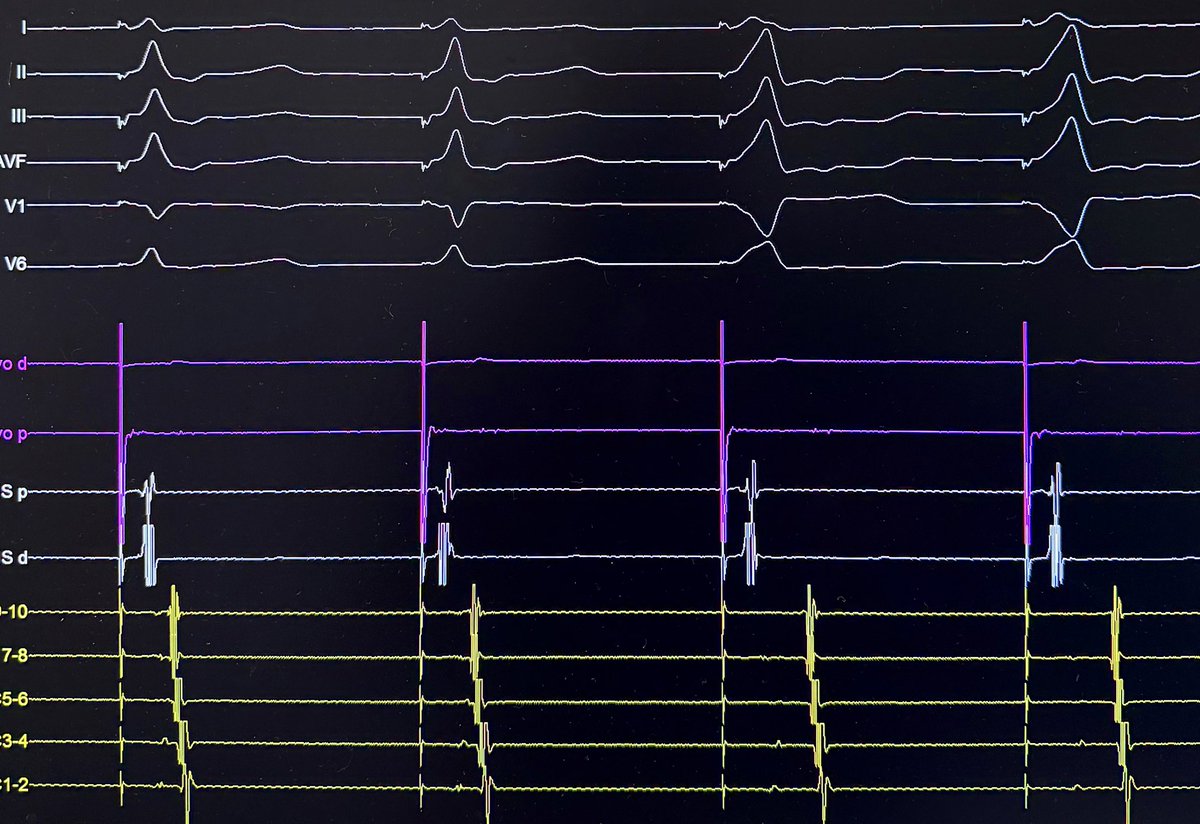

@Ecgloverr @ALFIEEP1 @ProfDConnelly @adribaran @SergioPinski @EPWaveDoc @KostekMilan @ArshadEP277 @UlhasDr @DrRoderickTung @DaveRichley @javadm20 Wide QRS tachycardia with LBBB morphology, in a young patient with axis and morphology similar to sinus rhythm. Altered basal ECG: QS V1-5. I'm inclined to think about supraventricular tachycardia with aberrance.

@IsaParam Two pathways(Lateral and Septal) initiated by Extra stim pacing on CS 9-10. Hard to rule out AT without calipers but VA does not seem to wobble too much(less likely). Lastly, AH jump seems to initiate the tachycardia further indicating that the AV node is part of the circuit.